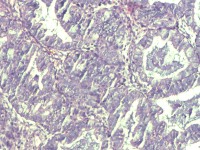

性别

女

年龄

55岁

临床诊断

异常子宫出血

一般病史

阴道不规则出血1月

标本名称

子宫内膜

大体所见

灰白色组织1堆、4*3.4*2.2CM大。

能诊断癌吗

图1

子宫内膜样腺癌

雾蒙蒙:

支持。